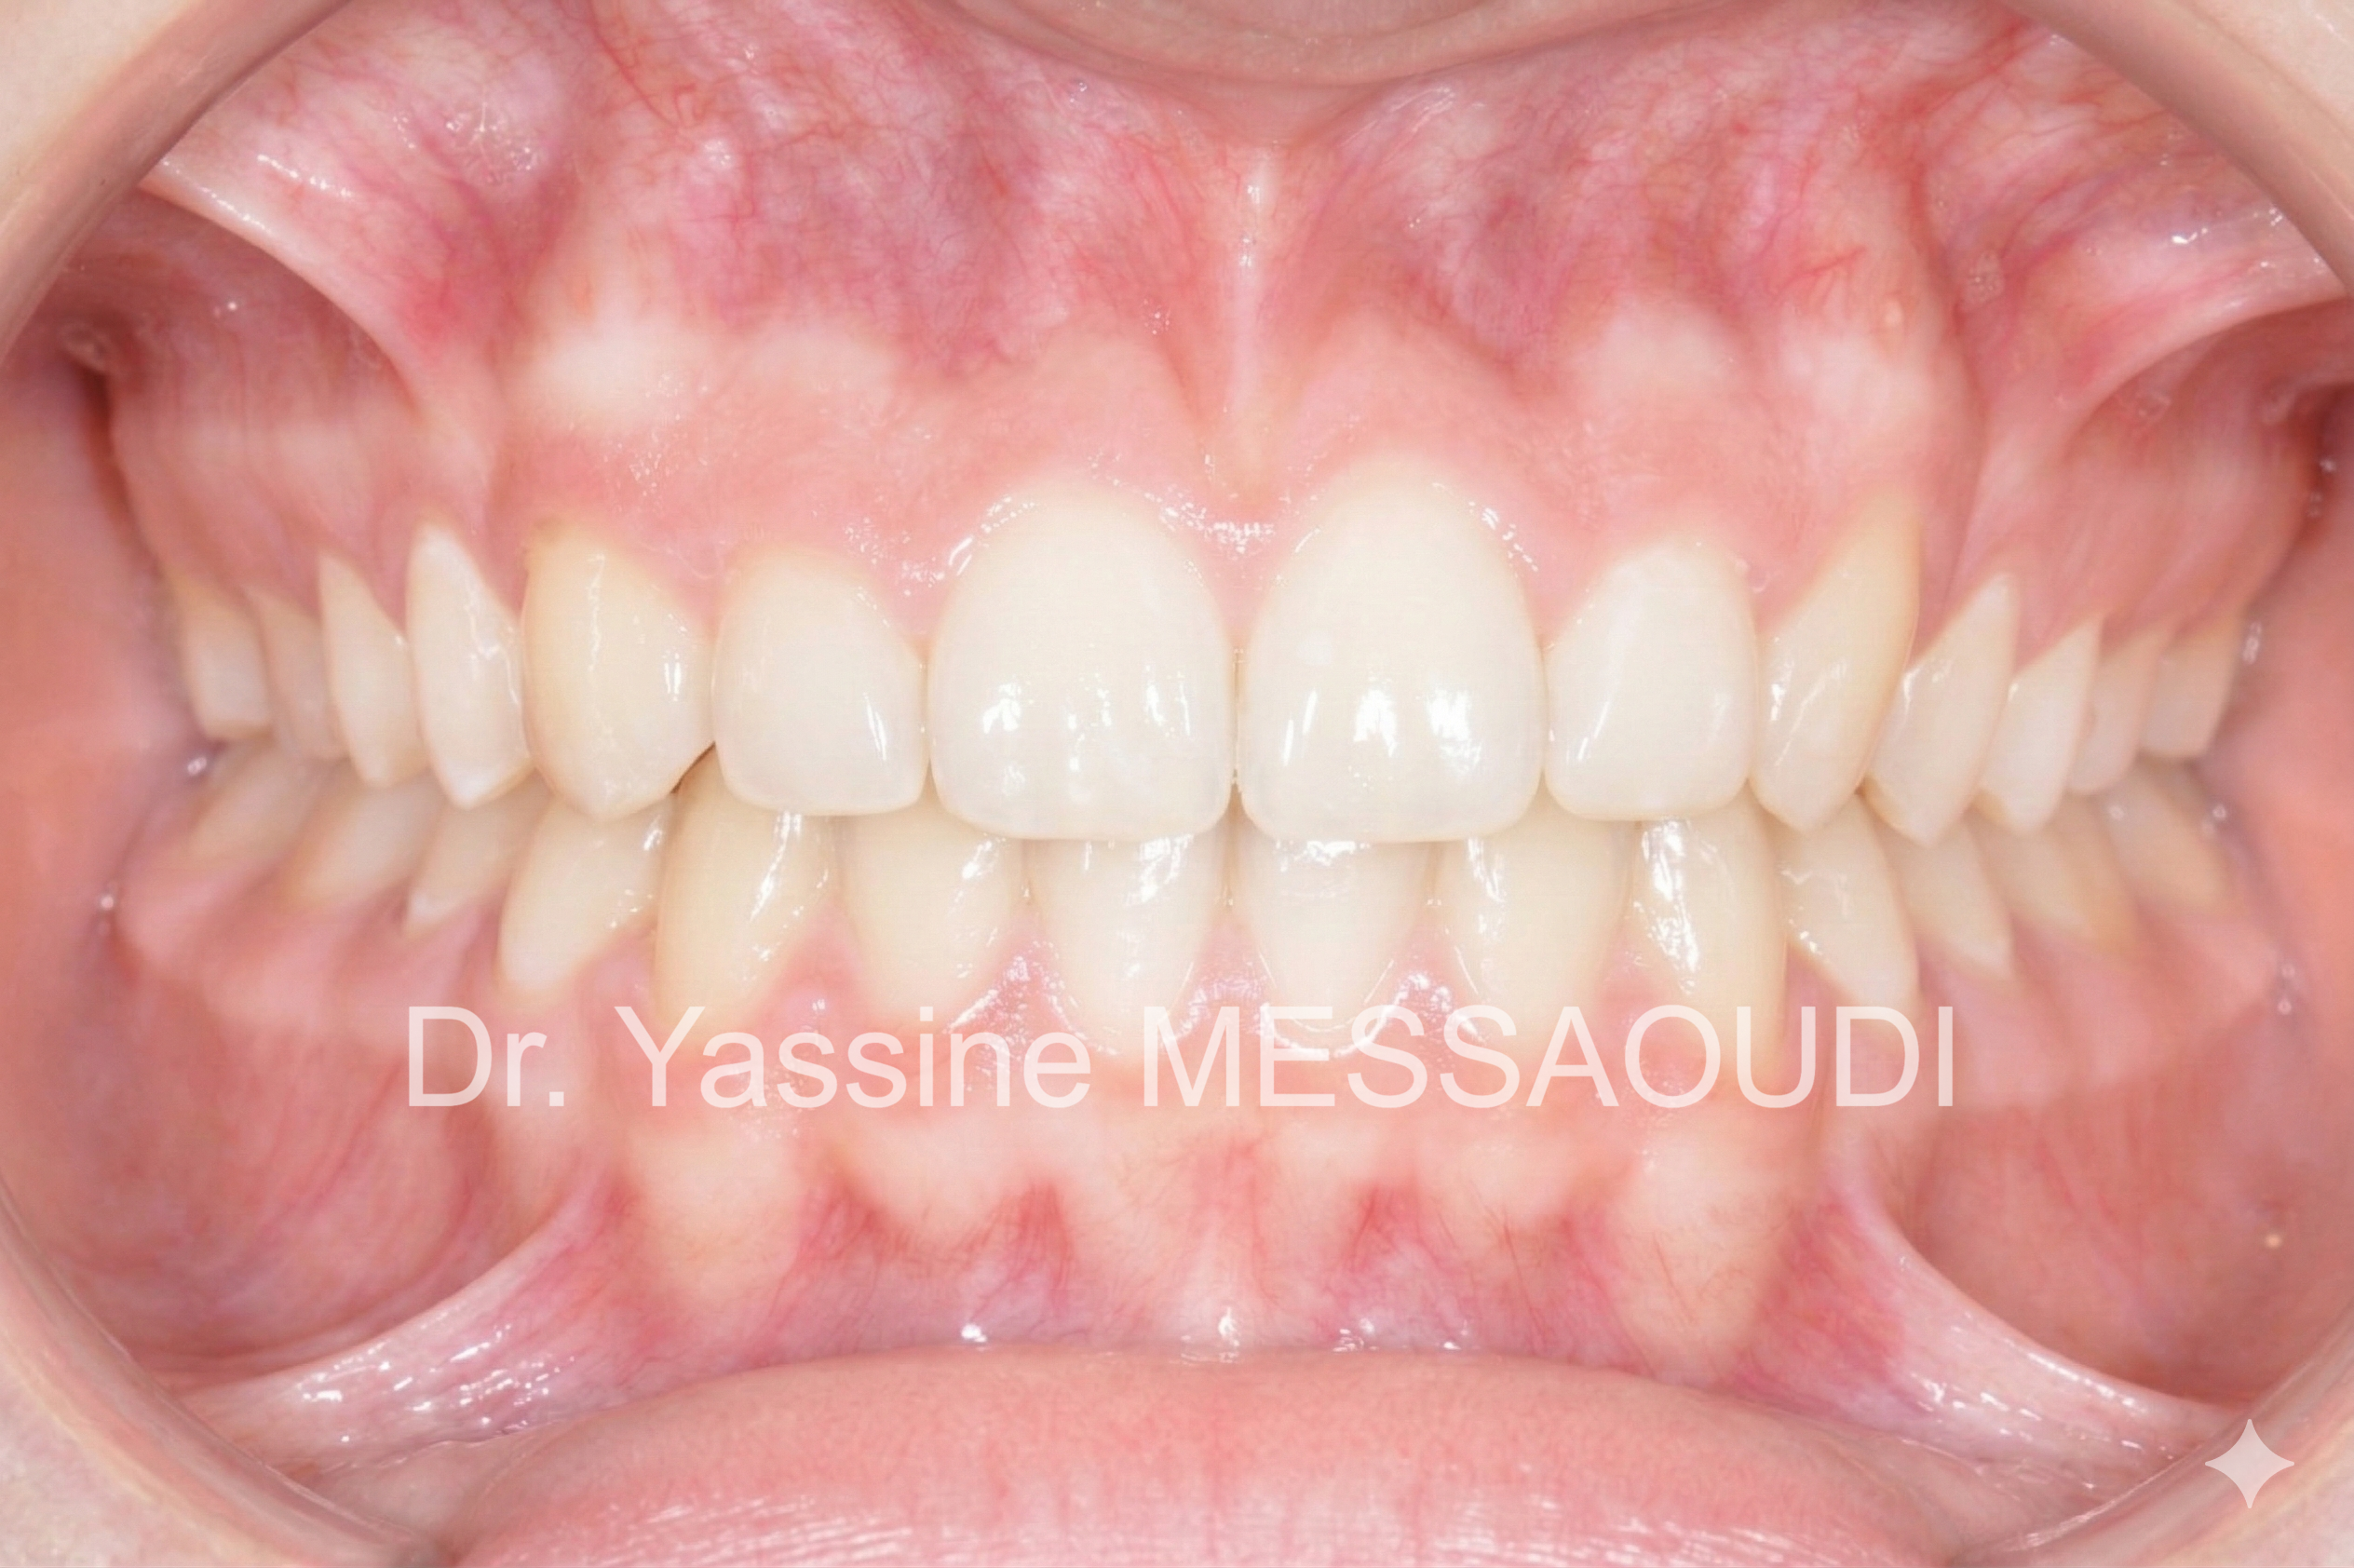

L'orthodontie vise à corriger les déséquilibres dentaires et cranio-faciaux afin d'améliorer la fonction, l'esthétique et la stabilité dans le temps.

Il ne s'agit pas uniquement d'aligner des dents, mais de concevoir un projet thérapeutique cohérent et individualisé, adapté à chaque âge de la vie.

Traitement de canines incluses palatines bilatérales